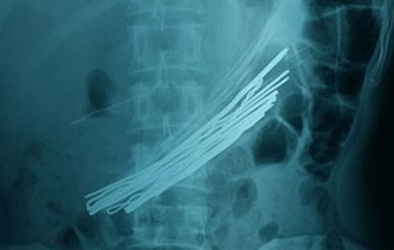

Cứu sống người đàn ông ‘ngáo đá’ nuốt nguyên cuộn dây thép dài 1,5m

(VietQ.vn) - Trong cơn ‘ngáo đá’, một người đàn ông 30 tuổi ở Huế đã nuốt cả cuộn dây thép vào bụng và phải nhập viện cấp cứu.